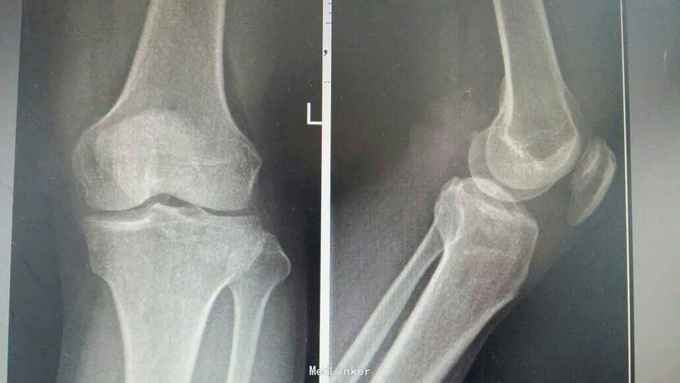

胫骨外侧平台骨折

外伤致膝关节肿痛活动受限3小时

膝关节肿胀,屈伸活动受限

胫骨外侧平台骨折塌陷2型,关节镜下辅助骨折复位内固定术